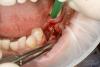

andr99 Опубликовано 22 июля, 2013 Поделиться Опубликовано 22 июля, 2013 Честно говоря, думал, что резорбция поболее должна быть..Аккуратно достали, спасибо за случай! Ссылка на комментарий

OMFS Опубликовано 23 июля, 2013 Автор Поделиться Опубликовано 23 июля, 2013 Честно говоря, думал, что резорбция поболее должна быть..Аккуратно достали, спасибо за случай!Пожалуйста!Вы правы. Снимок не соответствует действительности, имплантат болтался. Просто подковырнул его элеватором. Ссылка на комментарий